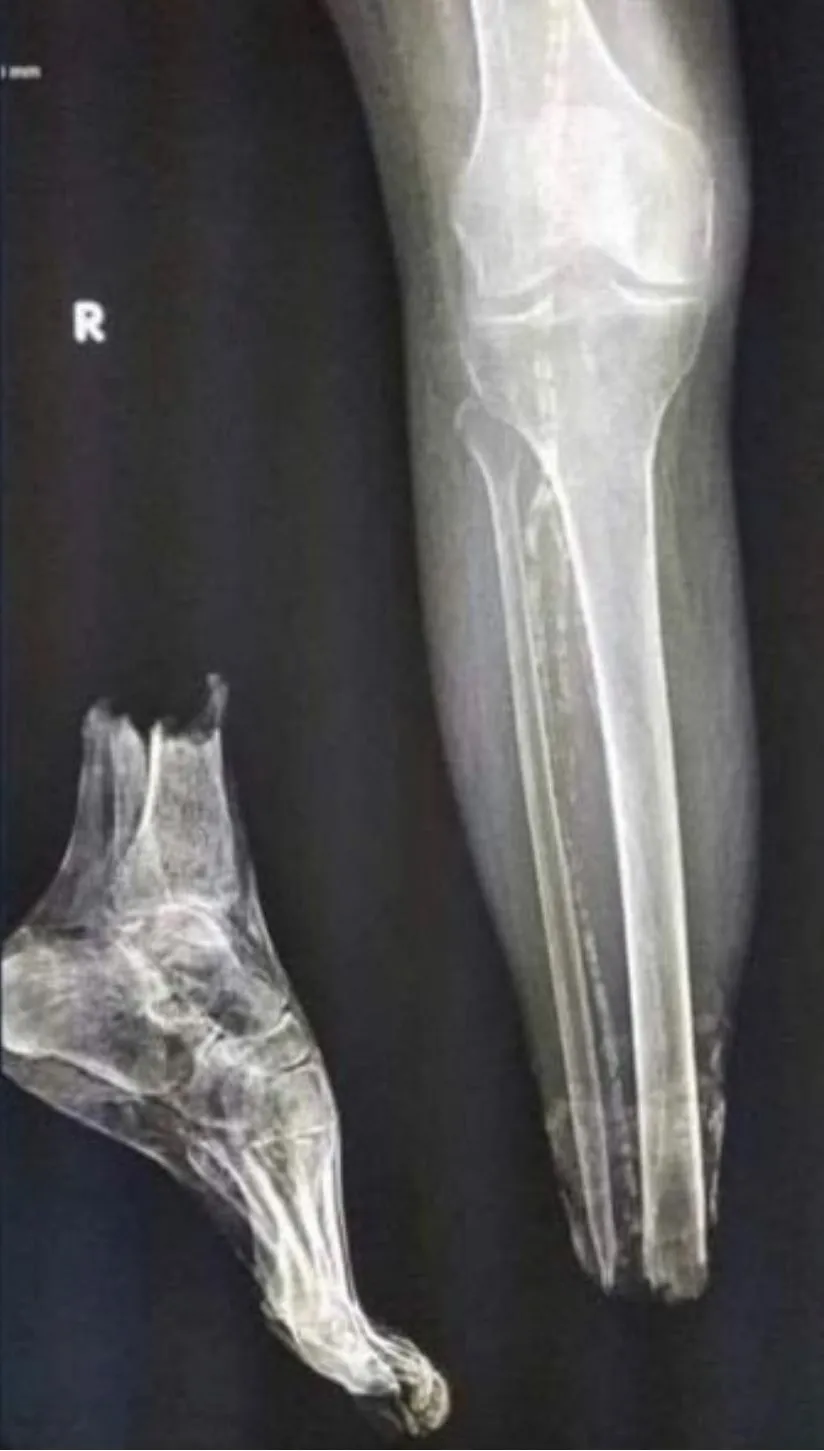

Acute or right?

Don't be obtuse

Looks like a clean break tbhScan has come back and our expert medical dept. think he should be ok with 7-10 days rest.

View attachment 184840